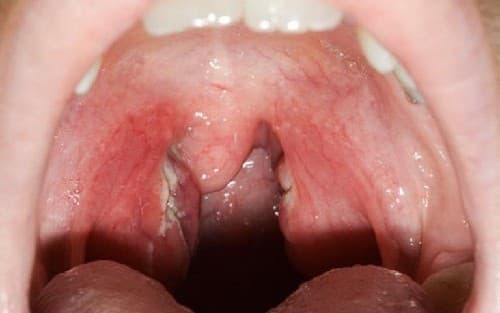

Triệu chứng bị viêm amidan có thể xảy ra ở mọi lứa tuổi

Viêm amidan có thể xảy ra ở mọi lứa tuổi và gây không ít phiền toái tới sức khỏe người bệnh. Chính vì thế khi thấy những triệu chứng bị viêm amidan sau đây người bệnh cần hết sức lưu ý, điều trị sớm để hiệu quả cao. Viêm amidan thông thường có thể tự […]